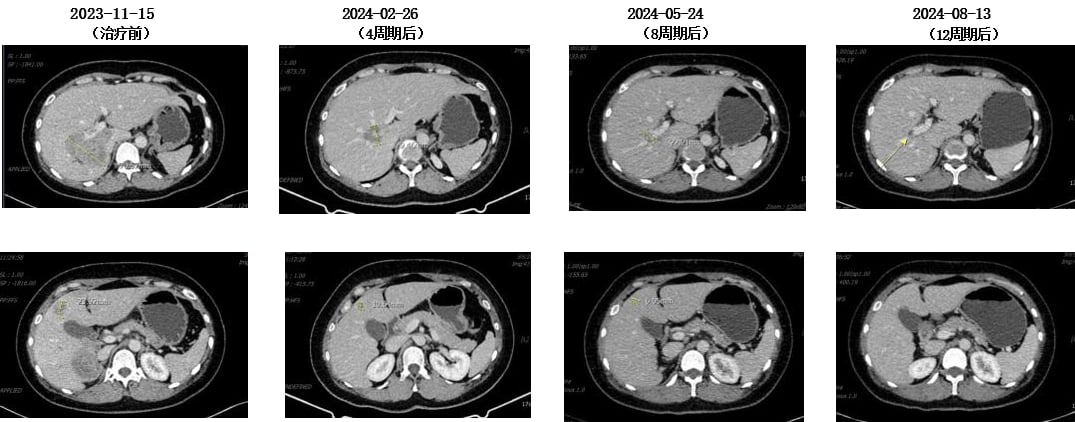

2023年11月,患者再次出现疾病进展,胸腹部CT显示肝内多发软组织肿物较前明显增多增大。肝穿刺活检病理再次确认转移性低分化腺癌,HER2(3+)阳性。

此时,患者入组了一项III期临床研究,比较FS-1502和T-DM1(恩美曲妥珠单抗)在HER2阳性不可手术切除的局部晚期或转移性乳腺癌患者中的疗效和安全性。她被随机分配到对照组,接受了14周期的恩美曲妥珠单抗治疗。恩美曲妥珠单抗是一种抗体-药物偶联物(ADC),它像一个“精准制导的化疗药”,通过抗体部分识别并结合癌细胞表面的HER2蛋白,然后将化疗药物精准地输送到癌细胞内部,减少对正常细胞的损伤。治疗后,患者肝功能异常I-II级,无骨髓抑制,疗效评价为部分缓解(PR)。临床试验不仅为患者提供了前沿治疗机会,也大大减轻了经济负担。